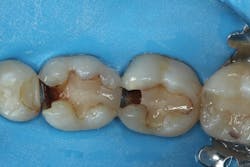

After removing the previous restorations, the distal axial wall of tooth No. 30 and the mesial axial wall of No. 31 had deep caries (figure 2). TheraCal LC (Bisco Dental)—a light-cured, resin-based liner containing calcium silicate (the active ingredient of MTA)—was placed over these areas of deep caries. A thin layer of the material was placed just at the areas of deep caries (figure 3) and light cured. Layers should be kept thin to ensure that the entire bulk of this opaque material cures, and placement should be limited to areas where needed in order to use the surrounding dentin for adhesive bonding. The dentin should be moist but not overly wet when TheraCal LC is applied to ensure that the material “sticks” to the tooth. Because this material is resin based, it is not necessary to cover this material with a separate resin-modified glass ionomer (RMGI) liner.

Figure 3: Placement of resin-based, light-cured calcium silicate liner (TheraCal LC; Bisco Dental)